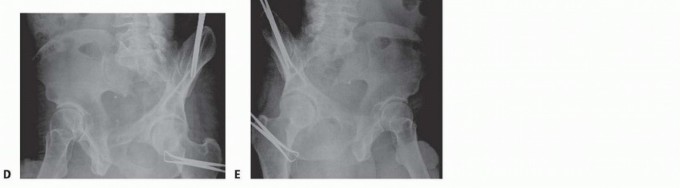

### FIG 5 • Appropriate AP (A), inlet (B), outlet (C), and Judet views (D,E) of the pelvis in a patient with pelvic trauma and wide pubic symphysis. (Courtesy of Jodi Siegel, MD, and David Templeman, MD.) 329 ## DIFFERENTIAL DIAGNOSIS Rami fractures Symphyseal strain Hip fracture Muscle strain or avulsion Lumbar fracture ## ACUTE MANAGEMENT The patients should be hemodynamically stabilized. The pelvis can be stabilized by placing ankles together with Ace wraps. Heels and ankles should be padded to prevent skin breakdown and ulcer formation. Placing a sheet across the pelvis at the level of the greater trochanters can be used to reduce the symphysis and temporarily stabilize the pelvis. The sheet can be affixed with towel clips to hold it with tension rather than tying a knot across the abdomen (see Cha 33). A pelvic binder can also be used in the same manner, but the authors prefer the sheet technique. ## NONOPERATIVE MANAGEMENT If minimal separation of the symphysis is present, the patient can be made non-weight bearing on the affected side and can be allowed to ambulate. Close radiographic monitoring should ensue, with weekly radiographs. Single-leg stance views can be used to help identify late instability. ## SURGICAL MANAGEMENT A diastasis larger than 2.5 mm indicates a disruption of the sacrospinous ligaments and thus an unstable pelvis. Open fixation of the symphysis stabilizes the anterior pelvis. 3 Open injuries can be stabilized with external fixation using iliac wing pins or Hanover pins placed at the level of the anterior inferior iliac spine. Refer to Chapter 33 for more details. Additionally, the technique of INFIX using pedicle screws at the anterior inferior iliac spine and a subcutaneously placed bar can also be used for obese patients. 17 In APC type II injuries with an intact hemipelvis, no posterior fixation is needed, and the symphysis is reduced and stabilized first. For type III injuries, if the innominate bone is broken, the anterior pelvic ring is reduced and fixed after the posterior ring is reduced and fixed. The anterior pelvic ring is reduced and fixed as a first step if the innominate bone remains intact. Indications for anterior stabilization for vertically unstable pelvic fractures include improving anterior stability to the pelvic ring, stabilizing a pelvic injury that is associated with an injury requiring a laparotomy, treatment of bone protruding into the perineum (ie, a tilt fracture), or in association with an acetabular fracture requiring open reduction. 13 ## Preoperative Planning The surgeon should review appropriate radiographic studies (AP, inlet, and outlet views and CT scan). Identifying all rami fractures and the presence of any pubic body fractures is essential, as this will help determine how to obtain a reduction as well as dictate the type of fixation necessary. The surgeon should plan to obtain stress views in the operating room to determine the stability of the pelvis if there is any question of stability. The surgeon should rule out the presence of a bladder rupture or urethral tear. If one is present, repair should be performed at the same time as internal fixation of the symphysis, if possible, to avoid a more complex late reconstruction. Any history of previous abdominal surgery or the presence of prior incisions should be identified before going to the operating room. The proper equipment must be available, such as C-arm, radiolucent table, large bone clamps, external fixation equipment, and a C-clam ## Positioning 330 The patient is placed on a radiolucent flat-top table with legs together to facilitate reduction of the symphysis. Fluoroscopic radiographs confirming the ability to obtain a good inlet and outlet views with the C-arm are obtained before preparing and draping the patient. Right-handed surgeons may prefer to have the C-arm on the patient's right side and the drill and instruments on the patient's left for easier access to the symphysis with the drill. Placement of a Foley catheter is needed to decompress the bladder; it can also be felt intraoperatively to help identify the bladder. Venodyne boots are placed on both legs if possible for deep vein thrombosis prophylaxis during the case. ## Approach Open reduction of the symphysis is performed with an anterior Pfannenstiel approach. ## TECHNIQUES